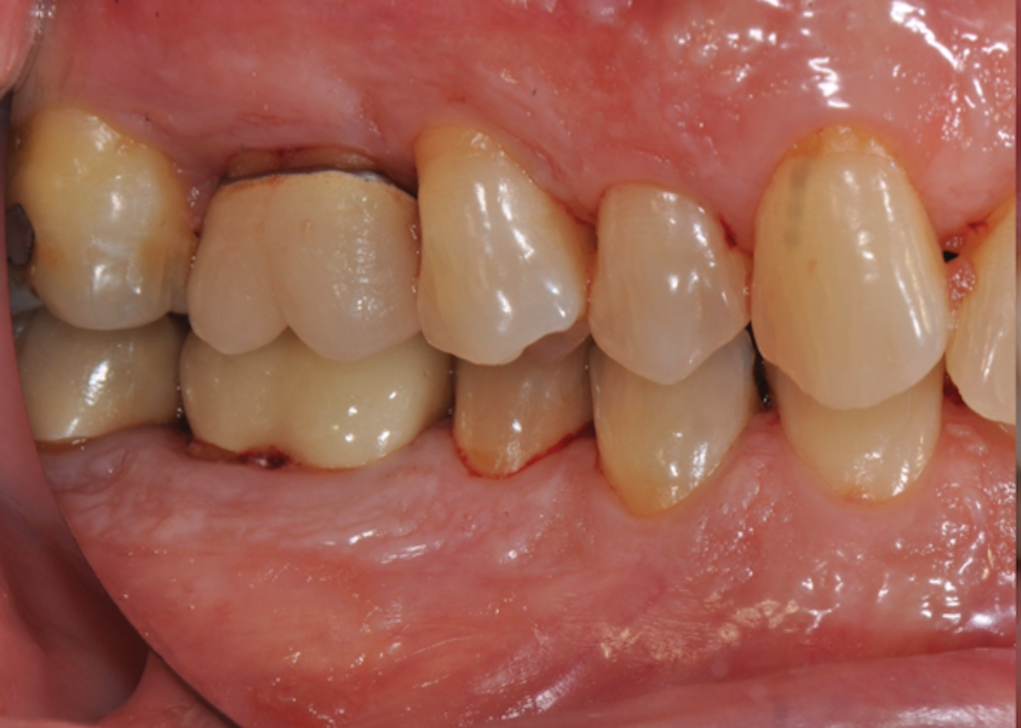

Fig 2. Pretreatment views: right lateral (Fig 2), frontal (Fig 3), and left lateral (Fig 4). Note: The maxillary right first molar (tooth No. 3) (Fig 2) would be identified as the most periodontally involved molar that was planned to be maintained.

Figure 2

Periodontal examination revealed generalized BOP and PDs up to 9 mm in the maxillary and mandibular molars with multiple furcations in each molar (Figure 2 through Figure 7). He presented with class I mobility in many posterior teeth and class II mobility in teeth Nos. 3 and 9 (maxillary right first molar and maxillary left central incisor, respectively). The periodontist decided to score tooth No. 3 for the PRS, as this was the most periodontally involved molar that was planned to be treated and maintained (Figure 2 and Figure 8). This tooth (maxillary right first molar = score 1) presented with probing depths of 7 mm (score 1); three total furcation invasions (score 3) (mesial [degree II furcation], buccal [degree I furcation], and distal [degree II furcation]); and a class II mobility (score 2). The total PRS for tooth No. 3 was 8, representing a "guarded" prognosis. Based on this score, the likelihood of not losing any teeth to periodontal disease for 15 years was 81%, and for 30 years the likelihood was just 56% (Figure 9).7